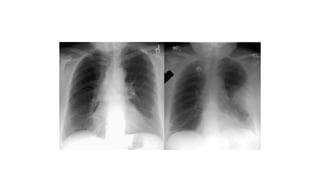

Diagnostic Tests CXR Chest radiographfindings in patient with pulmonary embolism Result Cardiomegaly Normal study Atelectasis Elevated Hemidiaphragm Pulmonary Artery Enlargement Pleural Effusion Parenchymal Pulmonary Infiltrate

Chest X-ray Eponymsof PE 29 Westermark's sign • Focal , demarcated oligaemia • Hampton’s Hump • A triangular or rounded pleural-based infiltrate with the apex toward the hilum, usually located adjacent to the hilum. • Palla’s sign • prominent right descending pulmonary artery